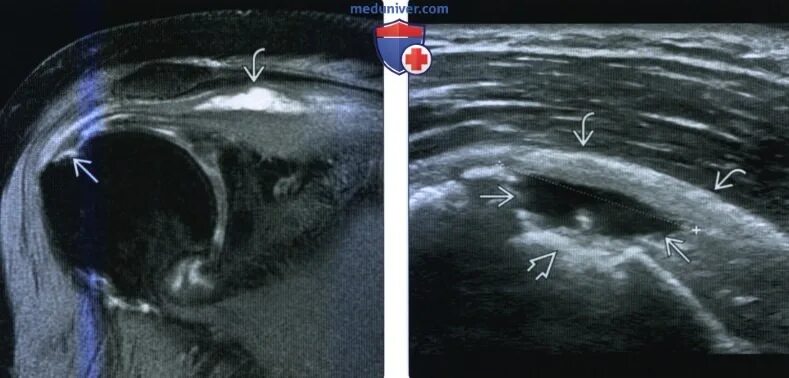

Частичный отрыв